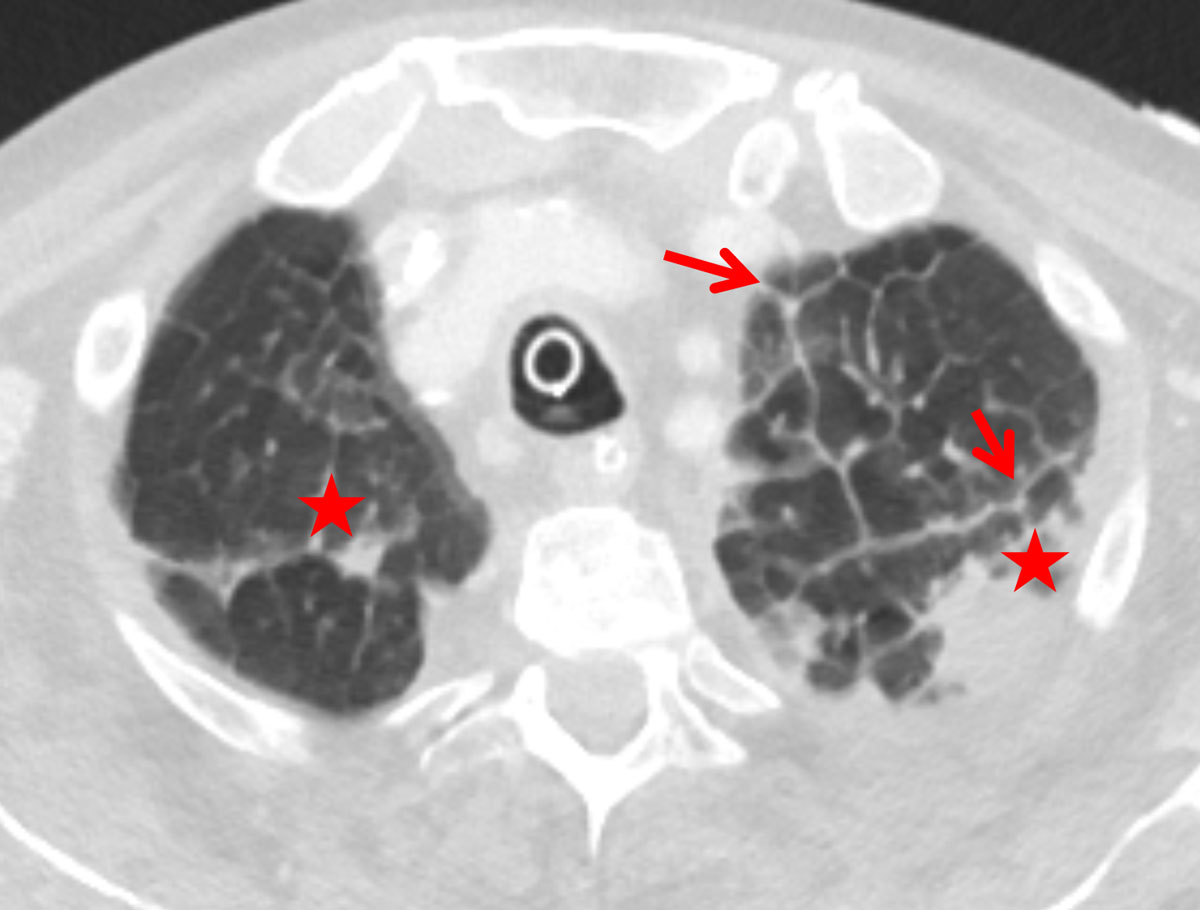

Interlobular septal thickening (IST) in the lung apex was present in of 81% and 76% of the cardiac and renal groups, respectively, which was significantly more than in the ILD group (26%, p <0.0001, figs 1–4 ). The distribution in the insufficiency group was more homogenous throughout the lungs than in the ILD group, in which the amount of septal thickening increased to 90% towards the lower lobes (table 2). The average thickness of the interlobular septa was rated between 1 and 2 with significantly thicker septal lines in the insufficiency group (1.45 ± 0.6) compared with the ILD group (1.28 ± 0.5; p <0.0001, fig. 3).

Figure 1 Thickened apical interlobular septa (Kerley B, red arrows) with transudation (asterisk) due to cardiac insufficiency in a 74-year-old female patient.

In this study, more than 80% of the patients with cardiac insufficiency and more than 70% of the patients with renal insufficiency presented with IST (Kerley B lines) in the lung apex. Miniati et al. described an identical distribution of the septal lines on conventional chest x-ray in the lower lungs among patients with heart or renal insufficiency [19]. While their distribution in the insufficiency group was homogenously throughout the lungs, the amount of Kerley B lines in our study increased to 90% towards the lower lobes in the ILD group. Findings of ILD predominate in the lung bases [8]. Patients with heart or renal insufficiency showed peribronchial cuffing due to increased capillary hydrostatic pressure or decreased oncotic pressure [1, 20]. One reason for the apical prevalence of the Kerley B lines in congested patients could be the redistribution of the pulmonary blood flow into the cranial parts of the lung, probably increasing the capillary pressure with resultant transudation. Kerley B lines are not a new sign in chest radiology, but their location in the lung apex is here described for the first time.